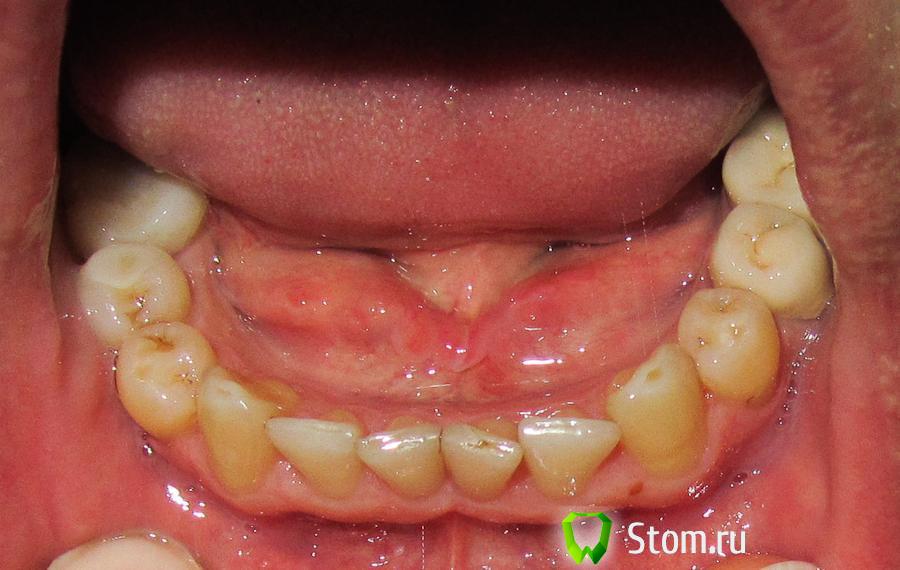

Oleg-Gru Опубликовано 22 ноября, 2011 Поделиться Опубликовано 22 ноября, 2011 (изменено) Доброго всем времени суток, уважаемые стоматологи! После успешного удаления сложной восьмерки, (проблема обсуждалась здесь: http://forum.stom.ru...__fromsearch__1 ) на днях завершил терапевтическое лечение своих зубов. Однако, спокойно спать не дают сомнения по поводу обнаруженных следов стирания резцов.Собственно, постановка вопроса проста - стоит ли сейчас обращать на это внимание?Это нормальное состояние резцов, для моих 40ка лет? Или все же стоит уделить этой проблеме больше внимания уже сейчас, не дожидаясь, как говорится, когда гром грянет? Заранее спасибо за уделенное моей персоне время и внимание. Изменено 22 ноября, 2011 пользователем Oleg-Gru Ссылка на комментарий

Salma Опубликовано 22 ноября, 2011 Поделиться Опубликовано 22 ноября, 2011 зубы с возрастом стираются, так оно и должно быть, когда это физиологическая стираемость то делать ничего не нужно, если патологическая, то снижается высота нижней трети лица, могут добавляться проблемы с височно-нижнечелюстным суставом, мышцами, такое состояние нужно лечитьу вас как мне кажется чуть более стерты центральные верхние резцы, особенно правый, все остальное неплохоприпатологической стираемости зубы, как правило, зубы покрывают коронками. Ссылка на комментарий

Oleg-Gru Опубликовано 22 ноября, 2011 Автор Поделиться Опубликовано 22 ноября, 2011 Судя по отсутствующим 4кам на верхней челюсти,пациент вчера был у ортодонта Просто забыл об этом.А так-то я согласна,проблемы прикуса налицо(е) со всеми вытекающими. Так то было не вчера, а лет 30 назад. Какие проблемы с прикусом вы видите ? Ссылка на комментарий